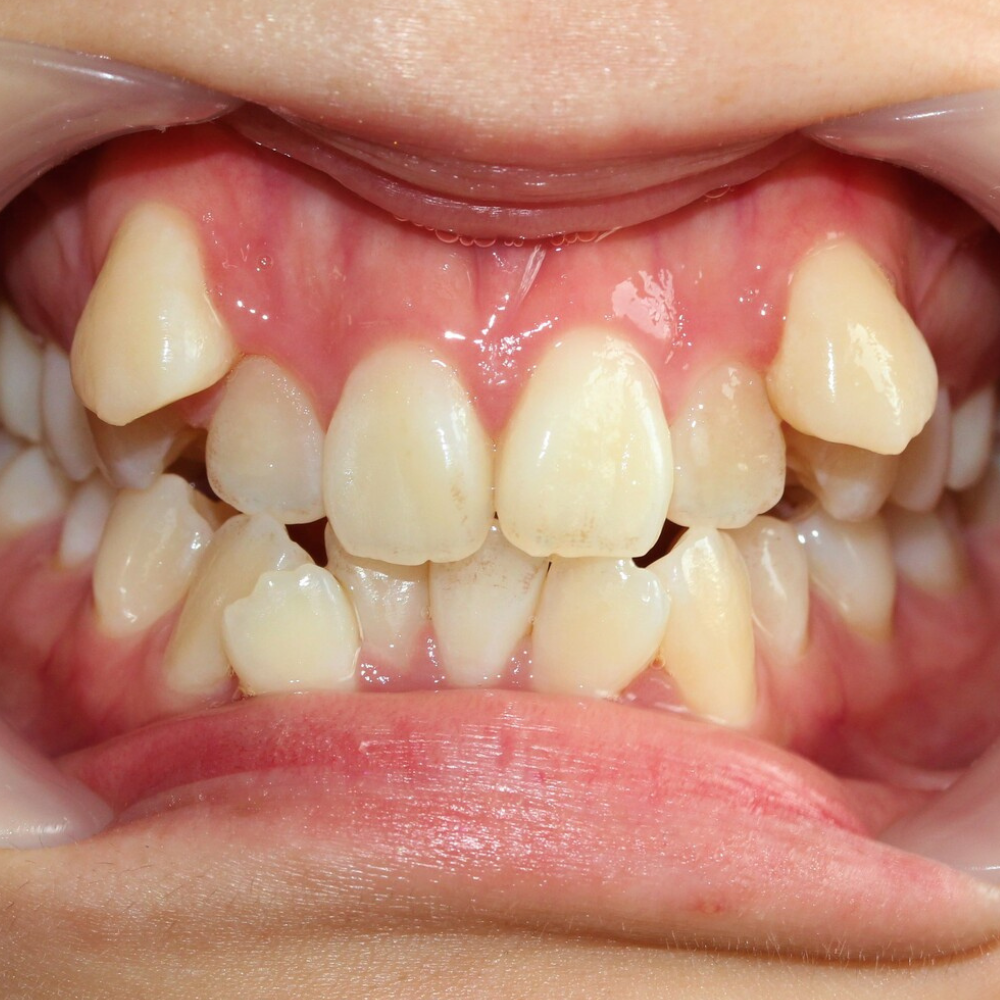

叢生(そうせい)は、ガタガタとかガチャ歯乱杭歯(らんくいば)ともいわれる、歯と歯が重なってデコボコした症状。

程度にもよりますが、不正咬合の中では最も「歯並びがガタガタしている」、そして「清潔感に欠けている」「笑顔がかわいくない」という印象のある症状です。

虫歯歯周病のリスクが非常に高い

歯が重なり合っている部分は歯ブラシの毛先が届きにくく、汚れ(歯垢)が溜まりがち。

そのため虫歯や歯肉炎、さらには歯周病へと進行するリスクが極めて高くなります。